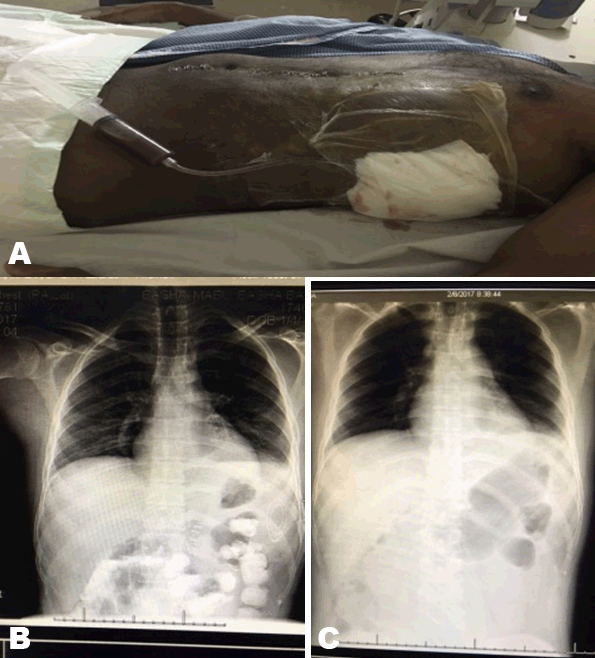

A 30-year-old Indian male presented to our emergency room, a RTA victim, with lower abdominal pain. Resuscitation started according to ATLS protocol and examination was unremarkable except for suprapubic tenderness, tear of glans penis and right side of scrotum. Laboratory workup showed raised renal functions. Focused assessment with sonography for trauma (FAST) showed mild free intraperitoneal fluid. X-rays showed bilateral lung contusions and pelvic fracture. Computed tomography (CT) scan without contrast was not done due to raised serum creatinine of 145 µmol/L and urea of 11 mmol urea per liter. Scrotal ultrasonography and Doppler were normal. Repeated hemoglobin was 8 g/dl, then ultrasound showed increased intra-abdominal fluid. He was prepared for laparotomy. 1.2 liters of free blood, normal solid organs except for 1 cm lateral capsular splenic tear with minimal bleeding were found. Splenic salvage was done with cautery and 2 pieces of pieces of local hemostats (Surgicel™). Resection anastomosis of 30 cm of ilium was done for transverse large mesenteric tear of the distal ileum. Wash with saline then, the abdomen was closed over drains. On the next day, he developed hematuria. Computed tomography (CT) scan with contrast showed normal solid organs. On day-10, blood workup and ultrasound were unremarkable. Drains removed and antibiotics were discontinued. He remained for wound infection care. On day-18, he had fever and subcostal pain. Clinically, he had mild left subcostal tenderness with no masses. Ultrasonography and abdominal contrast enhanced CT scan showed a subcapsular 12x6.5x3.6 cm splenic hematoma with no free intraperitoneal fluid, left pleural effusion and basal lung consolidation (Figure 1). Conservative treatment continued for 10 days and till complaining of pain. Follow-up CT scan showed no improvement. He was offered ultrasound-guided percutaneous drainage or splenectomy as alternative in case of failure of drain. 40 ml of turbid blood was aspirated and sent for culture. A 16 F pigtail catheter was left inside the cavity. Post procedure chest X-ray showed a left hydropneumothorax that improved later (Figure 2). The culture of the aspirate was negative. He did well. Regular catheter care with flushing with 5 ml saline. On day-9, the drainage was reduced to 5 ml and serous. The catheter drainage stopped after three days. Ultrasonography showed obliteration of the cavity. The catheter was removed. He was discharged in a good condition and came for outpatient department follow-up three weeks later and was free of complaints. He did not agree to do follow-up CT scan as he had it three times during the course of treatment. CBC and ultrasonography were normal. He has regular follow-up.

Figure 1: (A) Abdominal computed tomography scan with contrast, (B) A large splenic subcapsular together with left pleural effusion and basal consolidation, and (C) Follow-up scan, (D) Showed no improvement.